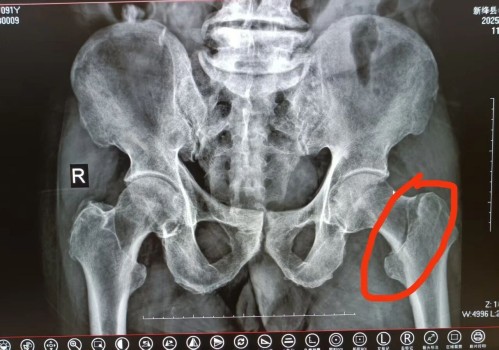

今年91岁的贾大爷(化名)在家中意外摔倒,左侧髋部剧烈疼痛,无法站立行走,被紧急送往新绛县中医院就诊。经详细检查,贾大爷被确诊为左侧股骨颈骨折,这对于超高龄老人而言,犹如“生命不能承受之重”——保守治疗需长期卧床,极易引发股骨头坏死、肺部感染、压疮、深静脉血栓等致命并发症,而手术治疗则因患者年龄大、身体机能衰退、手术风险高,让不少医院望而却步。

术前X片